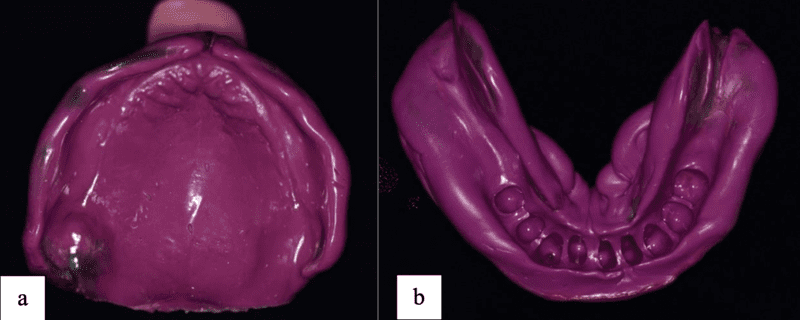

In the preparatory phase, oral hygiene maintenance was reinforced and a thorough description and discussion of various treatment options were given. Maxillary primary impression was taken using thermoplastic impression compound (Hoffman, Berlin, Germany) followed by alginate (Krompan, Lascod, Illinois, USA) for taking the final primary impressions of the maxillary and mandibular arches. Following this, type III gypsum (Elite Rock, Zhermack, Badia Polesine, Italy) was poured to form study models (Fig 7).

Following a three-month period of wound healing post-extraction, border moulding was conducted for both arches utilizing greenstick impression compound (Kerr, California, USA) with special tray. Final impressions were taken using regular body polyvinylsiloxane (PVS) impression material (GC Exaflex regular, GC America, Alsip, USA) for maxillary arch and mandibular arch (Fig 9). The impressions were casted using type III dental stone (Elite Rock, Zhermack, Badia Polesine, Italy) to fabricate master cast models (Fig 10).